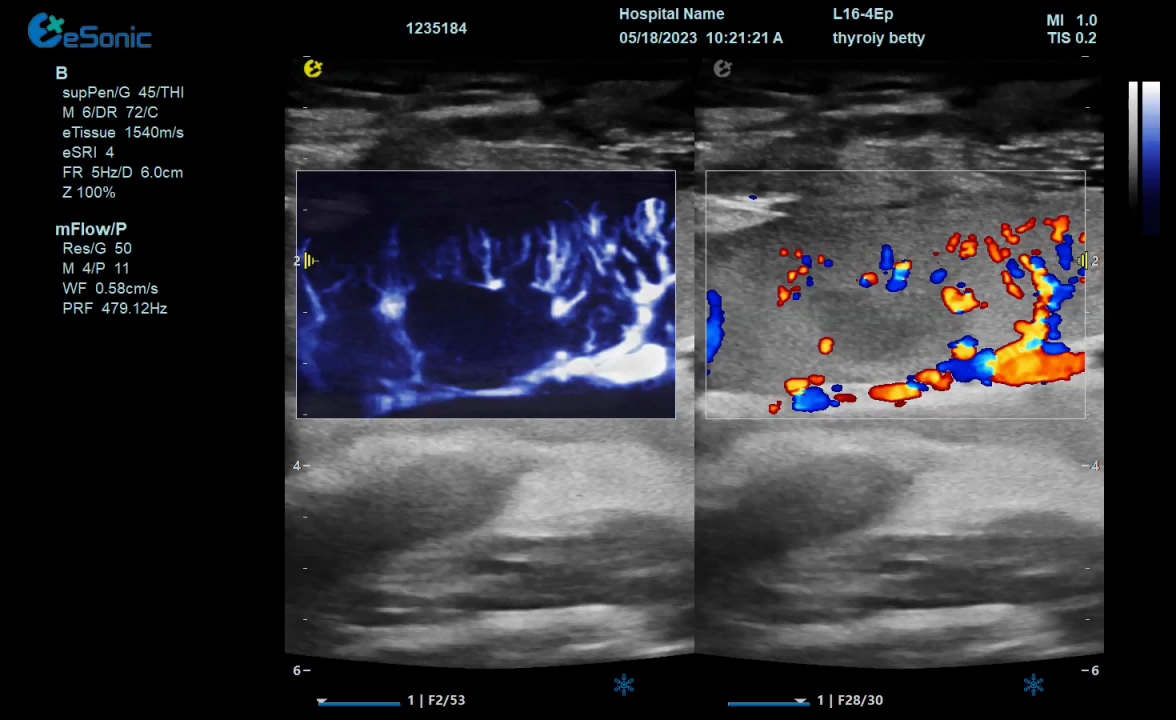

mFlow微血流显像技术,细节分辨率达100μm,支持频谱多普勒及VI血管指数定量。

mFlow新生儿颅脑